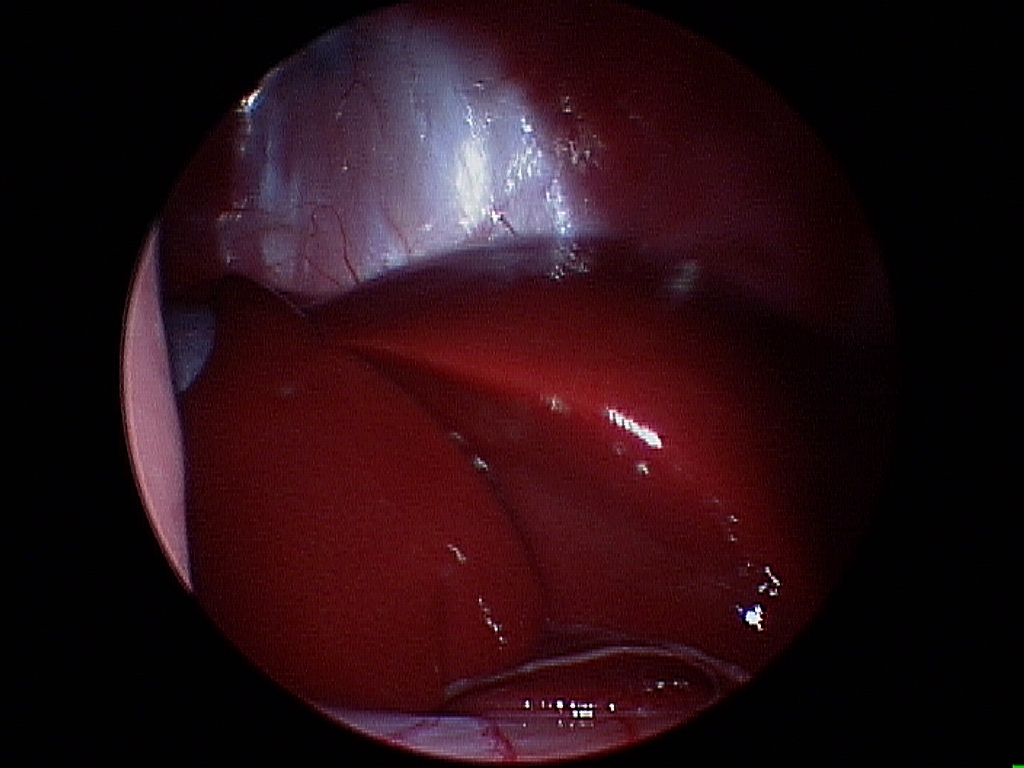

For the best possible outcome do not delay treatment! At this time, the gold standard approach is arthroscopic debridement (removal) of the fragmented cartilage and the surrounding diseased cartilage and subchondral bone. Curettage may allow the now vacant cartilage bed to fill in more quickly with what is called fibrocartilage. I likened the removal of the fragment to old wallpaper removal (very much oversimplified). Once the old wallpaper bubbles and tears, you need to remove all the damaged wallpaper in the periphery or else the wallpaper will continue to peel.

There are older techniques of opening the joint to get access to the cartilage flap, however the recovery time on this type of procedure is significantly longer than with arthroscopy. Also, potential complications are increased with an “open” technique than with arthroscopic techniques. Arthroscopy is a minimally invasive tool that allows us to both diagnose and treat this condition. Generally speaking the patient can walk on the surgery leg (even if both legs have surgery at the same time!) following an arthroscopic procedure. Generally 2-3 small ports are placed over the shoulder (2-4mm in length) and this allows us access to the joint and work within the joint.